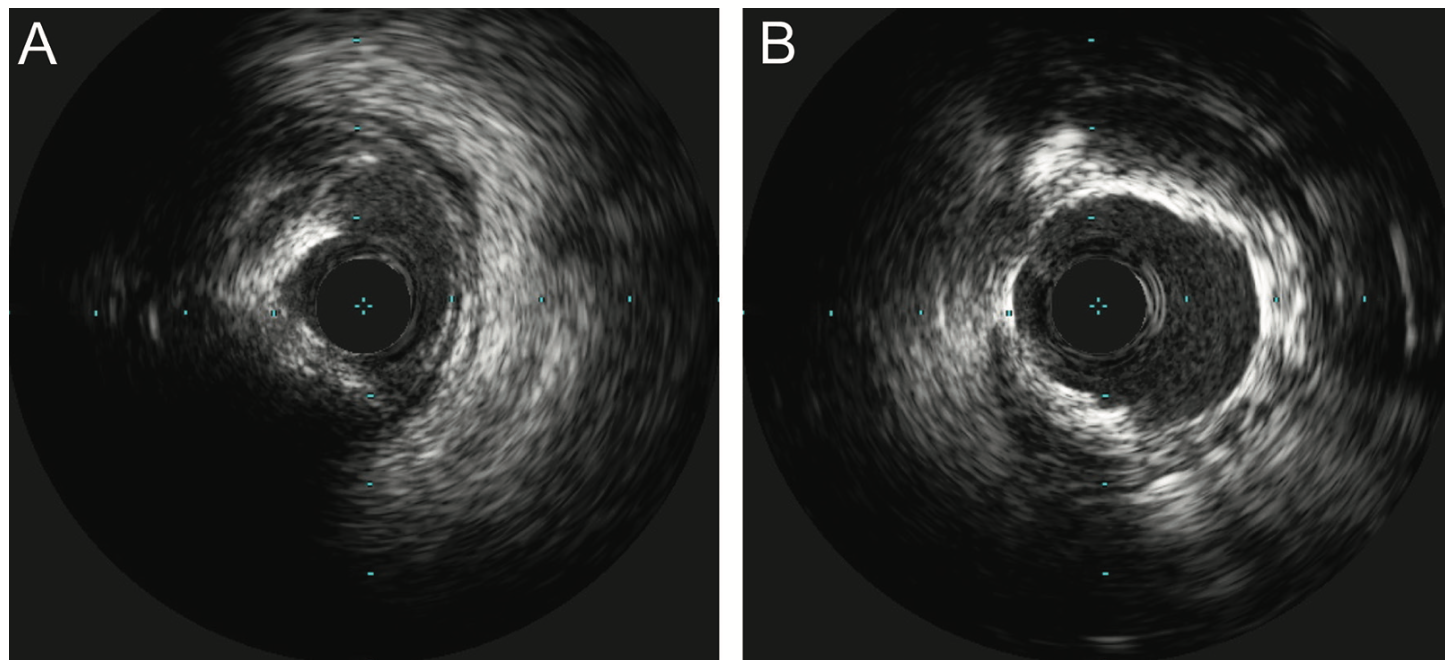

We proceeded with intervention to the RCA via right radial access using a 6 French (Fr) Terumo Glidesheath. Due to the critical ostial stenosis, a Terumo Runthrough wire was loaded in a 6 Fr Judkins right (JR)4 guide. There was severe pressure dampening on guide engagement and the wire was quickly advanced into the distal RCA. We attempted to deliver 2.5 and 2.0 mm Takeru semi-compliant balloons, but the balloons would not cross the proximal RCA stenoses. We then used a 1.5 mm Takeru semi-compliant balloon and dilated the ostial and proximal RCA, followed by 2.0 and 2.5 mm noncompliant balloons at 14 atmospheres (atm) (Figure 2). The ostial lesion was further dilated with a 2.5 x 10 mm Wolverine cutting balloon (Boston Scientific) at 8 atm. Intravascular ultrasound (IVUS) was performed with a Refinity catheter (Philips) (Figure 3A), and using a 6 Fr Guideliner (Teleflex), 2.5 mm x 38 mm and 2.5 mm x 22 mm Onyx Frontier drug-eluting stents (Medtronic) were deployed from the ostium to the mid RCA at 12 atm. The stents were post dilated with 3.0 and 3.5 mm Takeru noncompliant balloons at 18 atm. There was an excellent angiographic result with no residual stenosis (Figure 4A). IVUS showed well-expanded and well-apposed stents without evidence of dissection (Figure 3B), and the ostial RCA minimal stent area was 10mm2. The entire intervention was performed with only 65 mL of contrast dye. The patient was maintained on dual antiplatelet therapy with aspirin 81 mg and clopidogrel 75 mg daily. The patient returned for staged intervention to the LAD with rotational atherectomy and intravascular lithotripsy (Shockwave Medical) (Figure 4B).